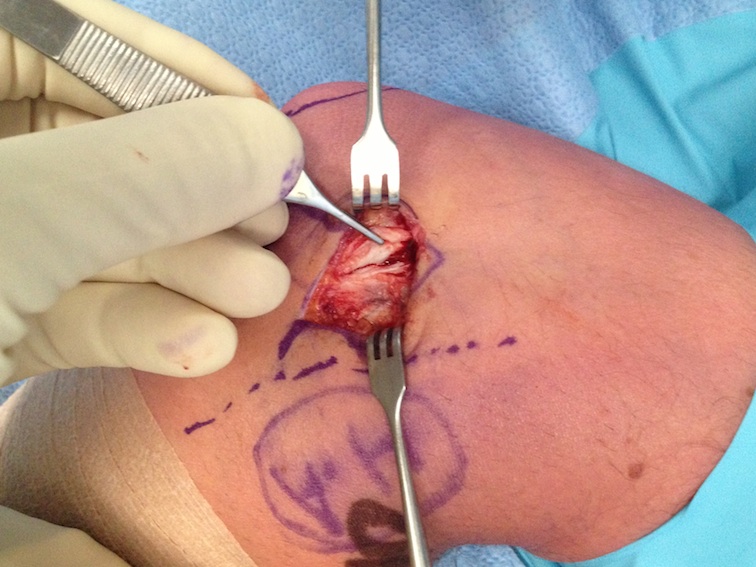

Open tennis elbow release

Technique

Incision centered on common extensor origin

- slightly anterior to radiocapitellar joint

- elevate ECRL (ECRL muscular at this point)

- ECRB is deep and posterior to ECRL

- detach ECRB from lateral epicondyle

- debride degenerative tissue and decorticate underlying common extensor origin

- +/- reattach ECRB with suture anchors